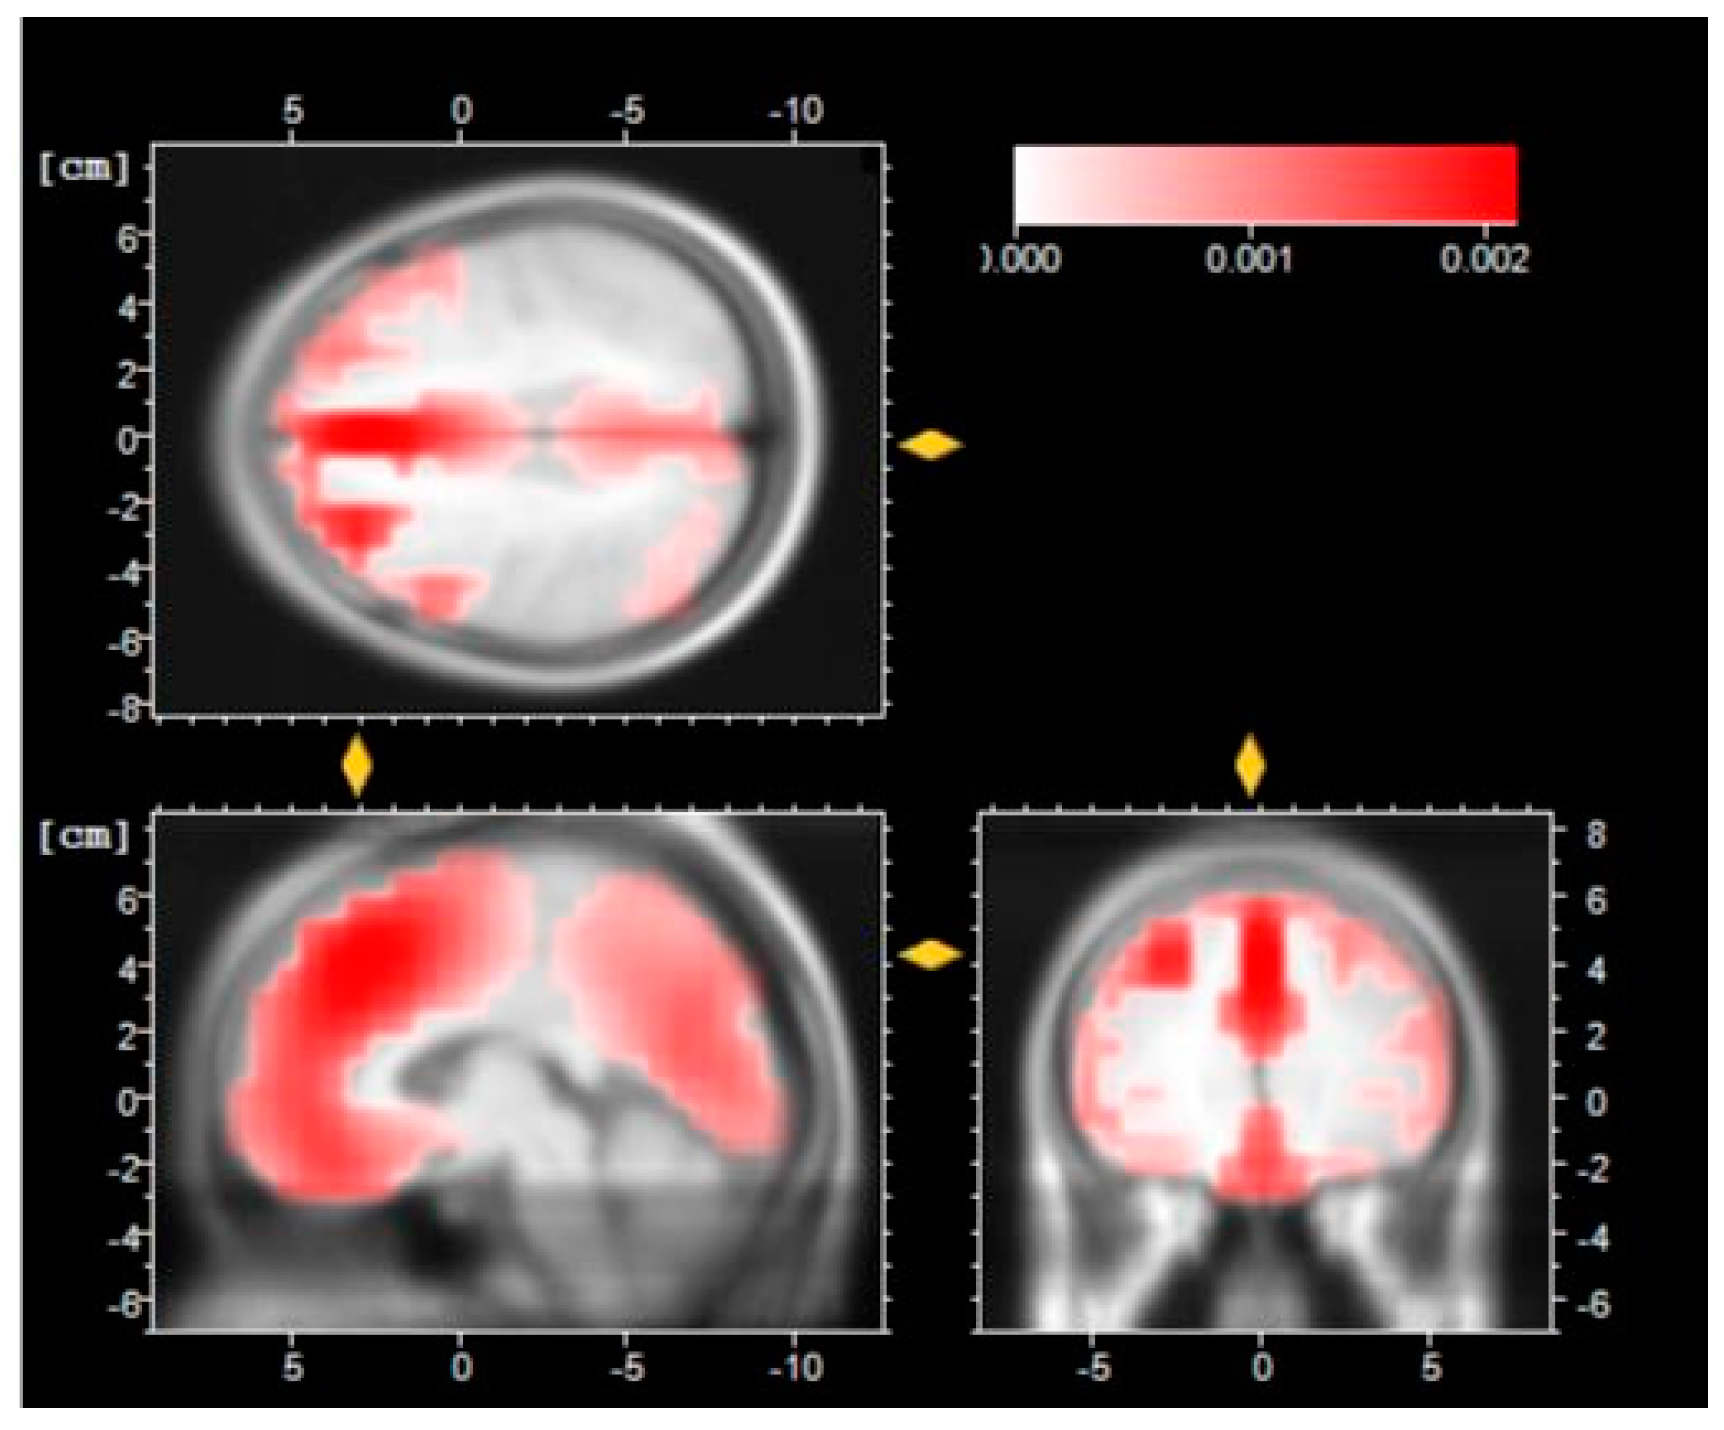

- Pascual-Marqui, R.D.; Esslen, M.; Kochi, K.; Lehmann, D. Functional imaging with low-resolution brain electromagnetic tomography (LORETA): A review. Methods Find. Exp. Clin. Pharm. 2002, 24 (Suppl. C), 91–95. [Google Scholar]